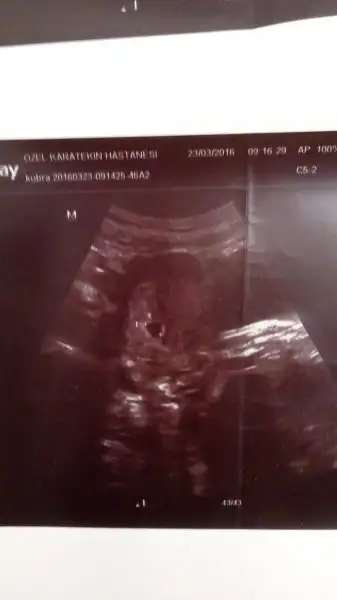

Benimkine de bakar misiniz :) ilkki5+6 gunluk digeri 7+3 gunluk.

günaydın arkadaşlar benimde goruntume bakabilir misiniz bu resim 5 haftalıkkenCnm plasentanin yerine göre ve bebeğe gore yorum yapıyorum.

Burda 6 haftalık goruntusu hangisinde daha anlaşılırsa ona bakın istedim şimdiden tesekkurler

Cevabı bana yazdiniz demi kusura bakmayın karışıklık olsun istemedim ben iki tane attim ayrı ayrı atabildim resimleri her ikisi de karındanUsg karındansa kız gibi,vajinalsa erkek gibi